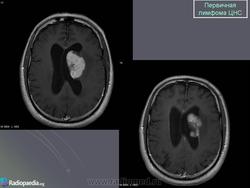

Первичные лимфомы ЦНС. Вс, 22/05/2011 - 21:45 #1 Катенёв Валенти... Не на сайте Был на сайте: 7 лет 5 месяцев назад Зарегистрирован: 22.03.2008 - 22:15 Публикации: 54876 Продолжение.Приложения:

Продолжение.